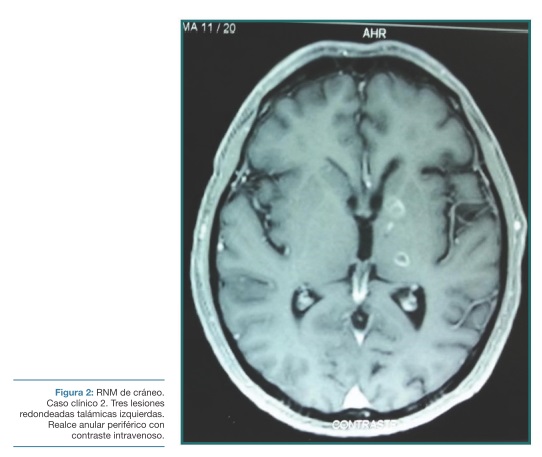

La resonancia magnética de cráneo mostró tres lesiones redondeadas talámicas izquierdas, bien delimitadas, la mayor de 12 mm, produciéndose realce anular periférico con contraste intravenoso, sin edema perilesional ni efecto de masa (Figura 2), compatibles con el diagnóstico de toxoplasmosis encefálica en este contexto clínico.

El caso clínico 2 se trata de un paciente inmunodeprimido que se presenta con el clásico síndrome sensitivo de Déjerine – Roussy, característico de lesiones talámicas contralaterales a las manifestaciones clínicas, acompañado de fiebre.

En este contexto clínico, el primer planteo es que la lesión talámica sea de origen infeccioso. Por frecuencia, por presentar lesiones características en la RM de cráneo y por la excelente respuesta al tratamiento específico instituido, se infiere que se trata de una toxoplasmosis encefálica.

El caso clínico 2 ilustra este raro síndrome, cobrando incluso mayor interés por tratarse de una lesión de origen infeccioso y no de origen vascular que sería, con diferencia, lo más frecuente.